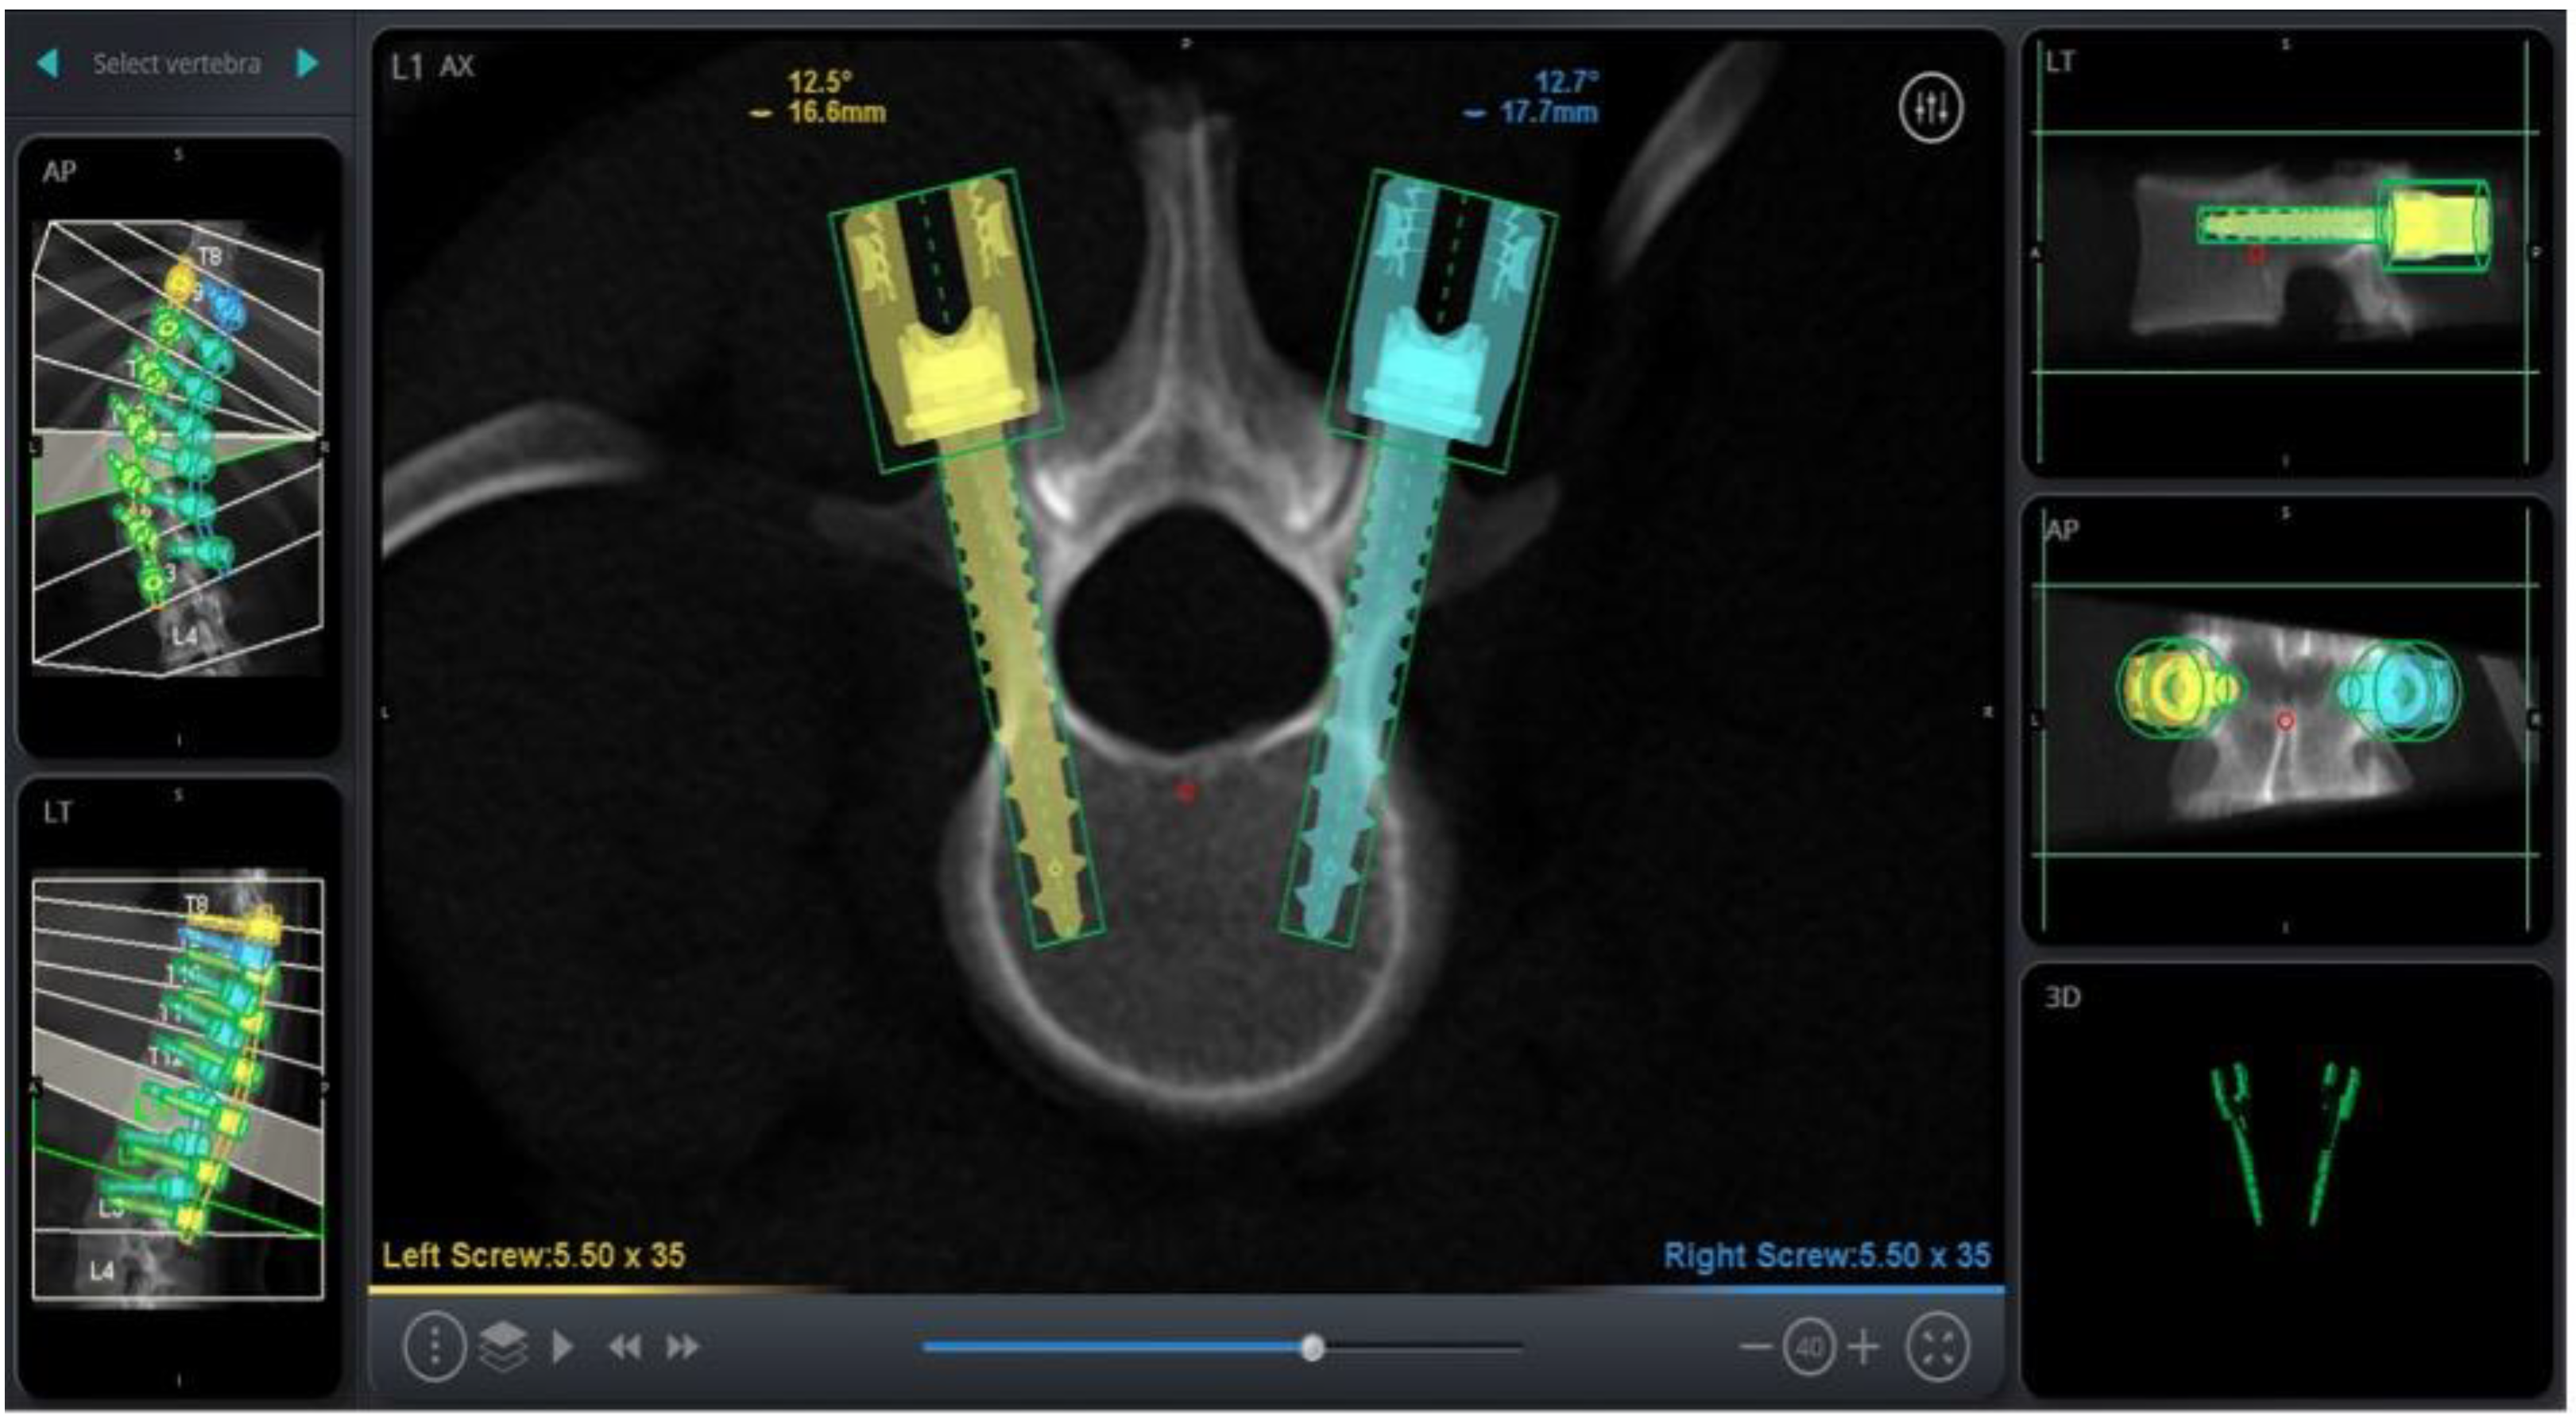

RAN technology relies on three-dimensional imaging and computer software to plan appropriate pedicle screw placement based on the patient’s anatomy (Figure 1). Once the patient’s anatomy is registered to the system, the robotic arm is sent to each screw placement trajectory location at the selected vertebral levels. Instruments are then sent through the robotic arm to guide placement, with navigation confirming positions in real time (Figure 2).

Figure 2. Pedicle Screw Placement Through the Robotic Arm using Navigation.